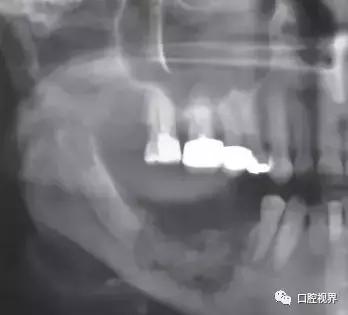

BRONJ的临床表现与放射性颌骨坏死类似,患者可能长期无明显症状,也可表现为颌骨疼痛或骨面裸露。典型的临床表现包括疼痛、骨面裸露、软组织肿胀、感染、牙齿松动、溢脓、瘘管形成。也可见骨面暴露但不伴感染症状的病例。其他症状还包括牙关紧闭、口臭、复发性脓肿、上颌窦炎、口腔上颌窦瘘等。当压迫周围神经时,可出现剧烈的颌骨疼痛或麻木,病情严重者甚至出现病理性骨折。